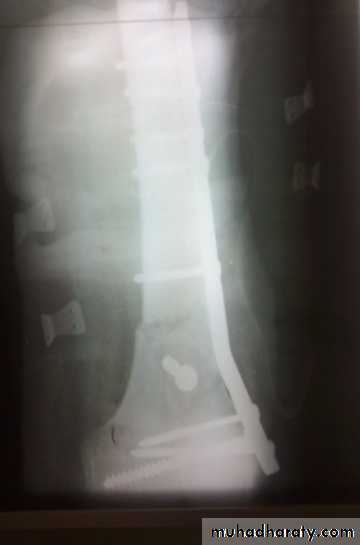

Tibial plateau fractures

Mechanism: medial or lateral bending force with axial loads, e.g. bumper fracture.

Doughy swelling of hemarthrosis.

Diffuse tenderness.

May be associated with knee ligament injury (collateral ligament, cruciate ligament).

X-ray:

One or both condyles may fracture with varying degrees of comminution.

C-T:

scan in complex fractures.

Treatment

Aspirate hemarthrosis.Minimally displaced fractures: compression bandage, gradual exercise,then functional brace and gradual exercise after 3 wks.

Displaced and/ or comminuted lateral or medial tibial condyle fracture

Treatment:ORIF.

Associated ligament injury repaired.

Bicondylar fracture: needs ORIF with plate and screws or external fixation.

Complications

Compartment syndrome.

Joint stiffness.

Knee instability.

Deformity: genu varum or genu valgum.

Secondary osteoarthritis.